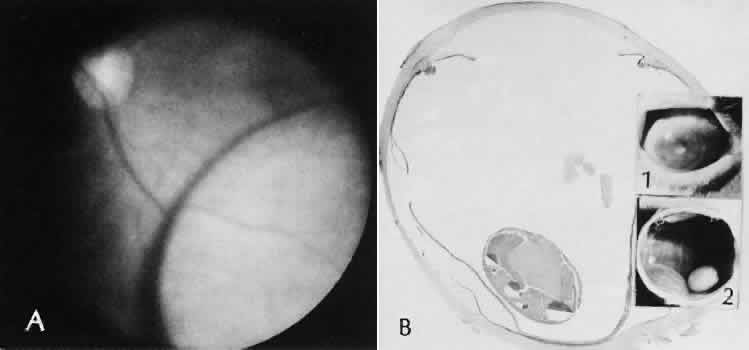

Fig. 31. A case of choroidal detachment. A. By fundus reflex, a large dome-shaped mass can be seen originating from the choroid. The differential diagnosis would include uveal malignant melanoma. In this case, the clinical findings were due to choroidal detachment from the sclera because of fluid accumulating in the suprachoroidal space following cataract surgery. B. The histologic section from another case of choroidal detachment illustrates the location (arrow) and extent of the detachment. In this case the detachment extends to the region of the ciliary body limited anteriorly by the attachment of the choroid to the scleral spur. The displacement of the ciliary body will result in apparent shallowing of the anterior chamber. (Hematoxylin-eosin stain; × 6.)

Iris or lens capsular incarceration into the wound and extending to the conjunctival space (Figs. 32 and 33) may act as a wick through which aqueous can escape, causing a flat anterior chamber. Histologically, iris, which is frequently recognized only by the presence of melanocytes, is seen in the limbal scar, in the limbal episclera, or in both areas.